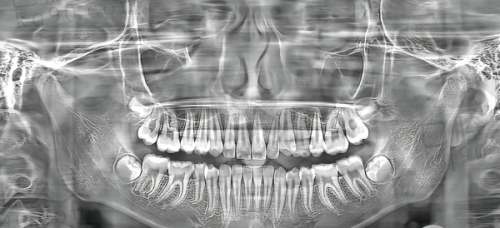

2. 进口高端口腔CT设备

进口高端口腔CT设备可厉害了,它能清晰地显示口腔内部的结构,包括牙齿、牙槽骨、神经等。医生通过CT图像,能更正确地诊断病情,制定治疗方案。比如说在牙齿种植前,通过CT设备就能了解牙槽骨的密度、高度、宽度等,选择更合适的种植位置和种植体。